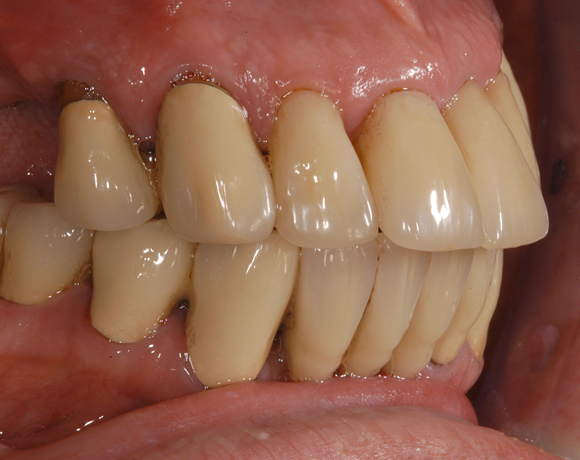

Im vorliegenden Patientenfall musste eine komplette Neukonstruktion der Oberkieferversorgung vorgenommen werden, da auf Grund parodontaler Probleme die Seitenzahnbrücken 15 – 17 und 25 – 27 nicht mehr zu halten waren. Die verbliebenen acht Frontzähne bzw. Prämolaren waren auch parodontal vorgeschädigt und es war ungewiss wie lange sie einzelne noch halten lassen. Um nicht bei jedem Verlust eines der Restzähne eine Neukonstruktion zu brauchen, hat man sich für eine Teleskopprothese entschieden. Für den Patienten war es allerdings nicht vorstellbar goldfarbene Primärteile im Mund zu haben, so wurde der Versuch unternommen diese aus e.max Press und Galvano Sekundärteilen herzustellen.